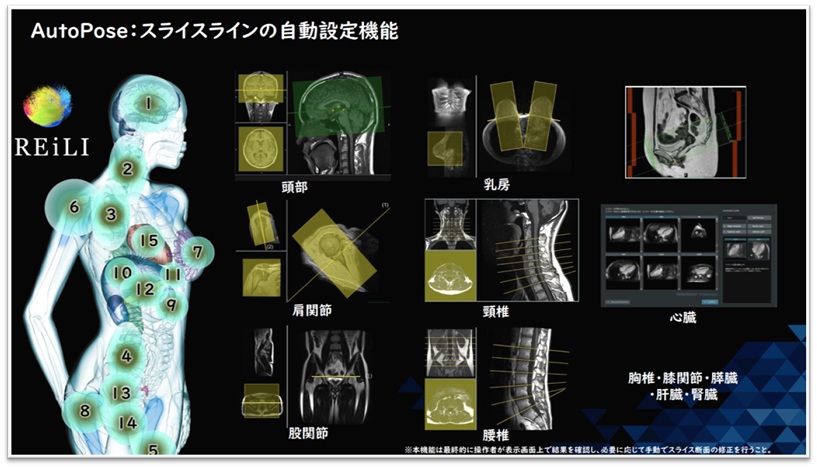

AIやDeep Learningの力は、画質改善だけにとどまりません。

撮影時の位置合わせをAIが自動で行ってくれることで、オペレーターの負担を軽減し、検査の効率もアップ。さらに撮影時間そのものも短縮できるようになりました。

つまり、AIは「より綺麗な画像」だけでなく「より快適でスムーズな検査」にも貢献しているのです。MRIは、AIによってますます患者さんに優しい検査へと進化しています。